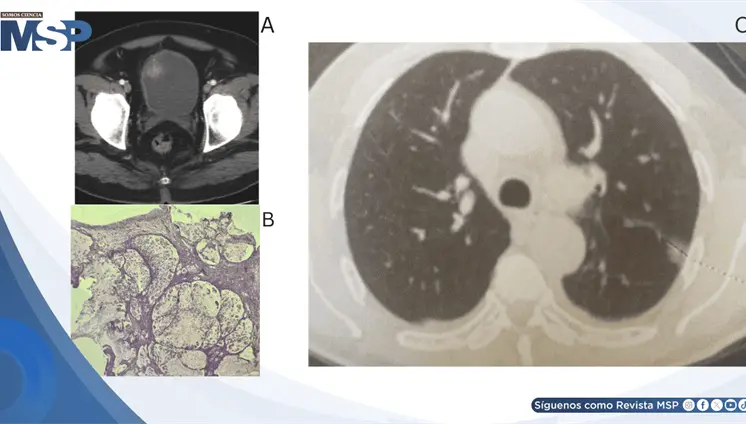

El estudio histológico confirmó un adenocarcinoma mucinoso de células en anillo de sello de vejiga con invasión muscular y diseminación metastásica pulmonar y ósea.

La paciente presentó cambios en el hábito intestinal y sangrado rectal con imágenes compatibles con lesiones estenosantes, inicialmente sospechosas de neoplasia sincrónica.